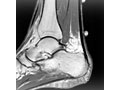

• Ultrasound . It may be used to see if there is a tendon tear or signs of tendinopathy.

• MRI scan . It may be used to check the tendon for signs of tendinopathy or a tendon tear. An MRI is also used to evaluate the heel bone.